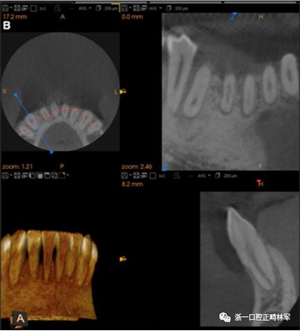

粘合保持器被移除,并放置固定裝置(圖15),僅限于患者要求的下頜弓。在第一階段牙周過程中,將結締組織移植物置于下頜右側中切牙的面?zhèn)取?個月后進行第二階段牙周過程(圖16)。包括有意識的垂直骨質評分以啟動區(qū)域加速現(xiàn)象,以及顯著的面?zhèn)群蜕鄠戎补且约m正骨開窗。隨著時間的推移,全維度弓絲及其表達的牙齒間扭矩差異顯著改善(圖17)。明智的鄰間減少之后,間隙關閉擴大接觸面,消除不美觀的黑三角。在脫粘之前也校正了牙齒排列和牙弓形態(tài)(圖18)。之前和之后的三維圖像(圖19)突出顯示在下頜右側尖牙面?zhèn)缺砻嫔瞎堑脑黾右约扒把姥栏恢玫母纳啤S捎谙骂M切牙的伸長被認為是不嚴謹?shù)?,因此輕度前牙開合沒有被矯正。

圖15.下頜右側中切牙區(qū)域軟組織移植前的初始排齊:A,正面視圖; B,咬合面視圖; C,軟組織移植2周后,初始牙周手術。

圖16.第二階段牙周手術階段,軟組織移植后2個月:A和B,這包括應用骨形態(tài)發(fā)生蛋白,故意骨質損傷引起局部加速現(xiàn)象,以及C和D,應用植骨漿液糾正牙槽骨的開窗(Colin Richman博士提供)。